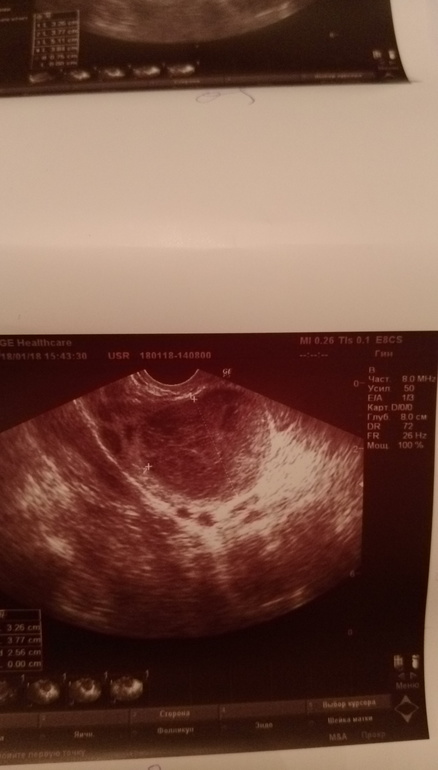

А что вам врач в диагнозе написал? У меня КЖТ вот как выгляди, если вы в этом понимаете. В кистозном вроде кровоток должен быть.

В прошлом цикле она была какая с кровотоком. В этом цикле уже эндометриозная

точно не жт, так как круглая, с четкими контурами. жт имеет неправильную волнистую форму, а вот какая, я не берусь

Больше похожа на эндометриозную ,кровоток есть по заключению?